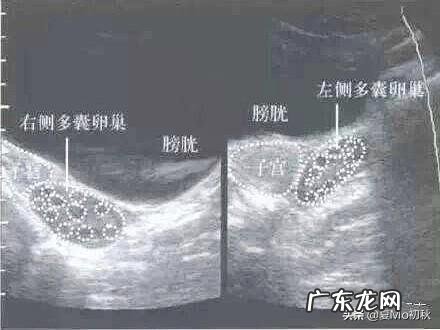

多囊卵巢通过B超监测,就可以看到卵巢两侧有很多卵泡 。基数在12个以上,都不会发育成熟,也不能排出体外 。但是抽血的时候,激素六项是正常 。有的也不会出现Y失调的现象 。甚至多囊患者可以怀孕 。

多囊卵巢综合征通过B超监测,也可以看到两边有很多卵泡,不会发育成熟排出体外,导致不孕 。而且抽血检查激素六项的时候,激素是不正常的,也就是内分泌系统失调 。